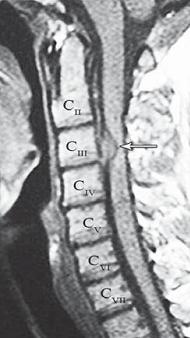

На МРТ № 18 наблюдаются грыжи межпозвонковых дисков в сегментах: — LIV-LV вентральной локализации с образованием каудального секвестра; при расположении межпозвонковой грыжи на один сегмент выше, «конфликт» с брюшной аортой был бы неизбежен; — LV-SI — дорсальная грыжа межпозвонкового диска, частично компенсированная спондилёзом МРТ № 19 ![]() МРТ № 20 ![]() На МРТ № 19 наблюдается дорсальная грыжа межпозвонкового диска шейного отдела позвоночника в сегменте СV-СVI с компрессией спинного мозга На МРТ № 20 наблюдается грыжа межпозвонкового диска шейного отдела позвоночника в сегменте CV—CVI и протрузия в сегменте CVI-CVII Замечу, что если грыжа межпозвонкового диска имеет достаточно большой размер и локализована в шейном отделе, то она способна вызвать не только соматические нарушения, но и даже психические расстройства. Причина кроется в сдавлении дурального мешка грыжей межпозвонкового диска (дуральный мешок — это герметичный соединительнотканный мешок, формируемый твёрдой мозговой оболочкой, в котором расположен спинной мозг). Как известно, спинной мозг не имеет болевых рецепторов. Однако вышеуказанная патология приводит к локальному устойчивому возбуждению определённых зон коры головного мозга. На субъективном уровне это может проявляться как постоянное чувство тревоги (так называемый «синдром ожидания»). Грыжи межпозвонковых дисков в грудном отделе позвоночника явление довольно редкое, но всё же наиболее опасное. Опасное потому, что эпидуральное пространство в грудном отделе позвоночника узкое по сравнению с другими отделами, в пределах всего 0,2–0,4 см по всей окружности дурального мешка (твёрдой оболочки спинного мозга). Поэтому даже небольшое грыжевое выпячивание может сдавить спинной мозг и вызвать тяжелейшие осложнения. Но, как уже говорилось, это явление в грудном отделе позвоночника редкое, поскольку высота межпозвонковых дисков довольно мала, всего около 3–5 мм, да и грудной отдел позвоночника менее подвижен по сравнению с другими отделами за счёт жёсткого рёберного каркаса, а значит, менее подвержен травматизации. МРТ № 21